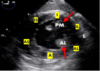

A

Trans gastric LV Basal Short axic view

0 Degree